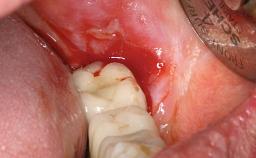

Peripheral Giant-cell Granuloma Associated with Peri-implant Tissues